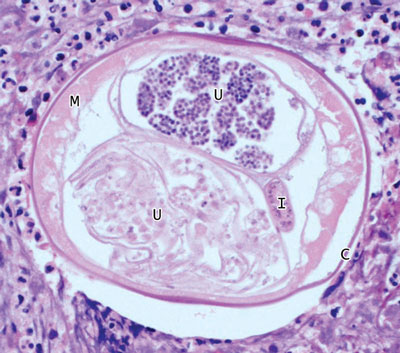

Lymphatic filariasis (LF) is caused by the filarial nematodes Wuchereria bancrofti, Brugia malayi and Brugia timori, which are transmitted between definitive human hosts by multiple mosquito vectors and have varying geographical distributions. LF is common in tropical and subtropical regions — an estimated 120 million people in 81 countries are infected, a third of whom have overt clinical disease.1-2 About one-third of those infected reside in India, a third in Africa, and the remainder in the Americas, South-East Asia and the Pacific, including many of Australia’s neighbours and countries with which Australia shares strong migration links.1 It is difficult to estimate prevalence accurately, but according to antigenic studies, prevalence of LF infection in India (the country with the greatest disease burden) is 5.66%.2 Endemic LF transmission in Australia has not been reported for over 50 years.3All three of the patients described were originally from countries endemic for LF, and their cases highlight the need for clinicians to be aware of the likelihood of LF being imported into Australia. The patients presented with recurrent inguino-scrotal pathology, with or without associated systemic symptoms, emphasising the difficulties of diagnosing this infection.

The diagnosis of symptomatic LF requires strong clinical suspicion. Careful ultrasound may identify the random movement of adult worms in dilated lymphatics, known as the “filarial dance sign” (FDS). This is particularly useful in a patient with scrotal symptoms and is considered the gold standard investigation for detecting viable adult worms;6 however, in Patient 3 this did not lead to the diagnosis.

A blood film and serological evaluation are alternative diagnostic options. In most endemic areas, circulating microfilariae (filarial larvae) exhibit nocturnal periodicity (coinciding with peak feeding of local mosquitos) and are best seen on blood films taken between 10 pm and 4 am. If nocturnal samples are not feasible, then provocation with diethylcarbamazine may enhance microfilarial detection 1–2 hours later. Pacific Island infections (except Papua New Guinea) are subperiodic, with maximal microfilaraemia in the late afternoon, and show unresponsiveness to provocation. Importantly, patients with the chronic manifestations of LF often have low levels of circulating microfilariae, resulting in lower blood-film sensitivity.7